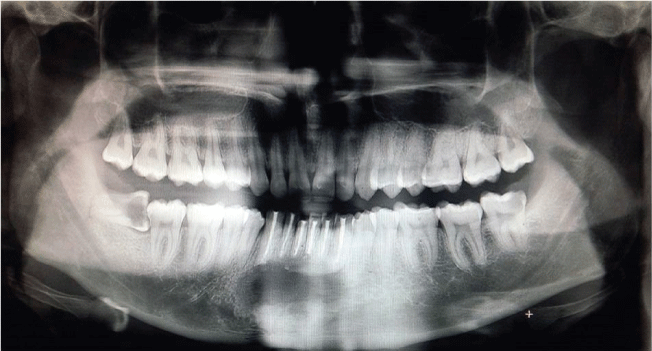

图1:骨扫描显示下颌骨前侧有大的桡骨囊肿

矫形扫描图(图1)显示下颌骨犬齿间区域(从33延伸到43)边界清晰的单房透光性。由于OPG是二维成像方式,可见在下颌骨中央区域的脊柱干涉。因此,选择三维计算机断层扫描来了解下颌骨颊、舌皮质板的前后伸展和完整性。CT图像(图2-4)显示除了一些小的穿孔外,舌皮质完好无损,与前下颌骨相关的颊皮质完全缺失。囊肿全长5x4x3 cm,由骨至软组织。经全身检查及血常规检查,提出6颗累及牙在局麻下采用囊肿摘除+根尖切除+三氧化二矿骨料逆行充填的治疗方案。患者在手术前对所有6颗受损牙齿进行了根管治疗,分别为31、32、33、41、42、43颗。